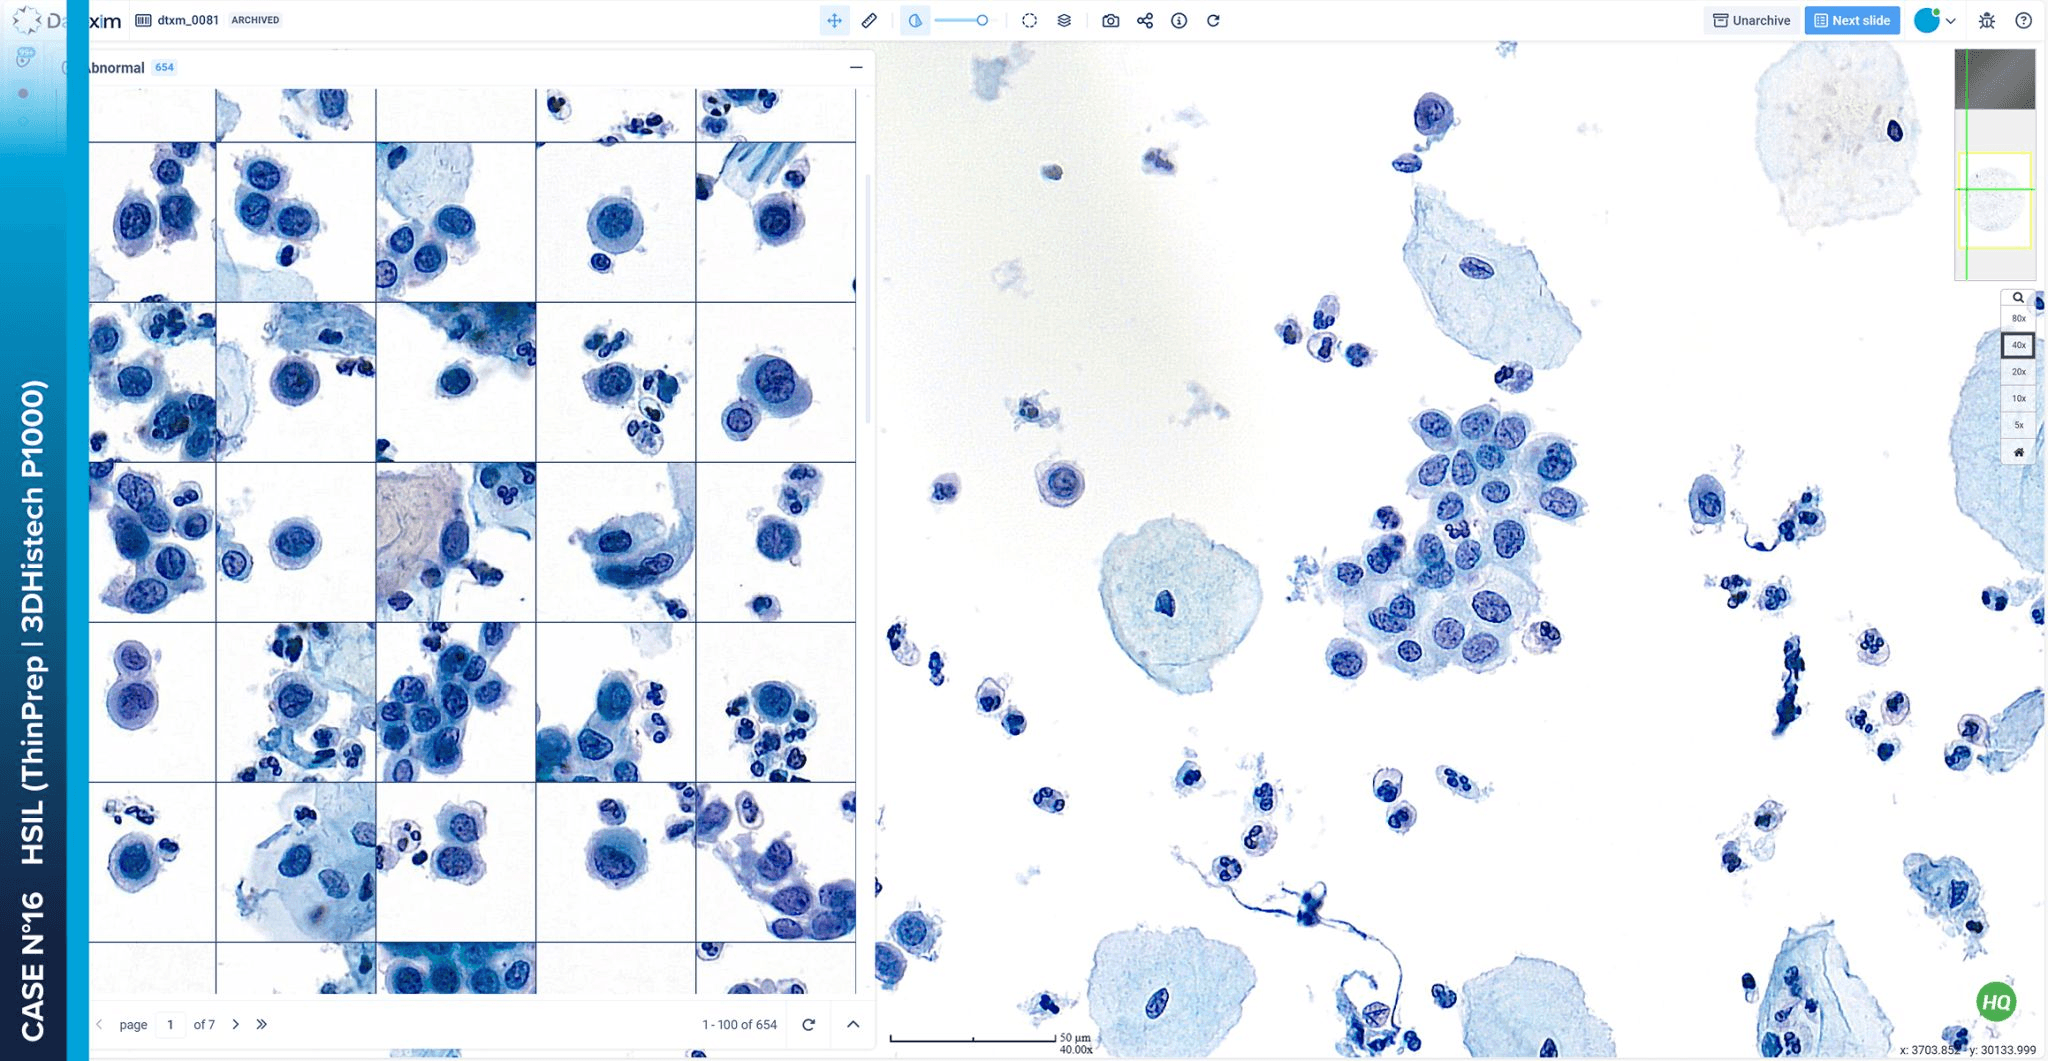

CytoProcessor® is a revolutionary AI-powered system that brings digital cytology to the forefront of cervical cancer screening. It uses powerful AI algorithms to automatically analyze digitized cytology slides, rapidly identifying and classifying abnormal cells.

CytoProcessor® is a revolutionary AI-powered system that brings digital cytology to the forefront of cervical cancer screening. It uses powerful AI algorithms to automatically analyze digitized cytology slides, rapidly identifying and classifying abnormal cells.

This smart system prioritizes the most diagnostic relevant cells, allowing pathologists and cytotechnologists to focus on what matters most. With CytoProcessor®, you can say goodbye to the microscope and hello to a faster, more accurate, and more comfortable workflow.

This smart system prioritizes the most diagnostic relevant cells, allowing pathologists and cytotechnologists to focus on what matters most. With CytoProcessor®, you can say goodbye to the microscope and hello to a faster, more accurate, and more comfortable workflow.

Easy to Use

CytoProcessor® IMS runs seamlessly on existing workstations and enables secure access from anywhere. Its intuitive interface maximizes efficiency, allowing users to review relevant cells with fewer clicks and streamlined navigation.

Easy to Use

CytoProcessor® IMS runs seamlessly on existing workstations and enables secure access from anywhere. Its intuitive interface maximizes efficiency, allowing users to review relevant cells with fewer clicks and streamlined navigation.

Easy to Use